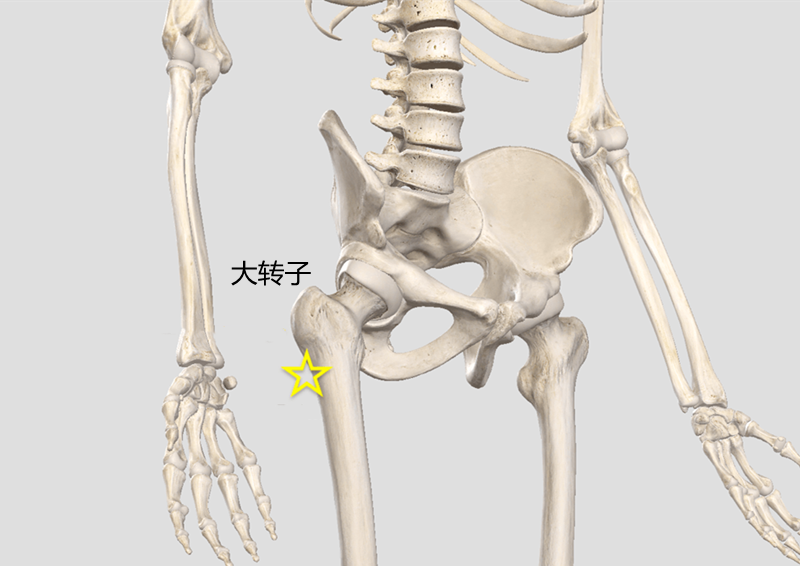

这些症状都指向髋关节滑囊炎,也叫大转子滑囊炎。大转子就是臀部侧面可以摸到突出的骨骼。早期X光很难发现问题。如果不积极治疗,发展下去有可能引起跛行,站立不稳,长短腿,甚至股骨头坏死。